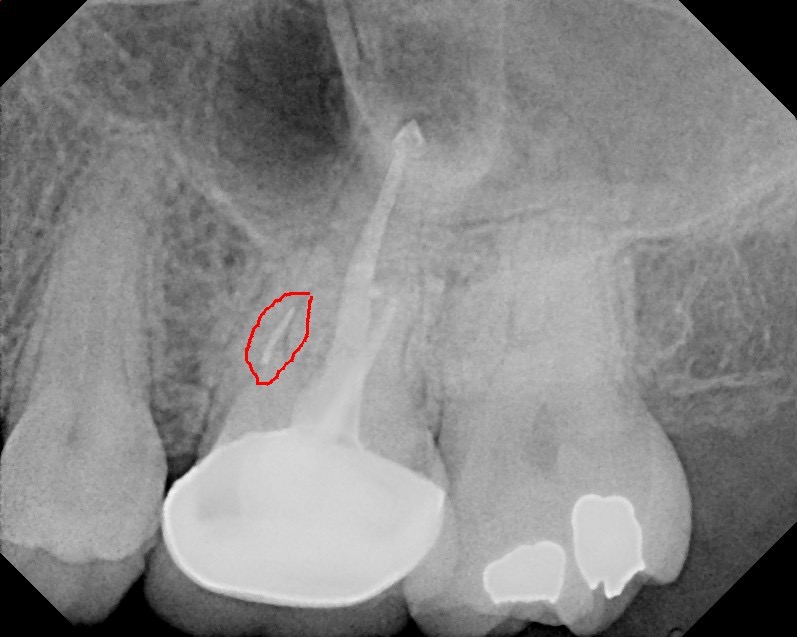

Previous root canal with separated file in the MB root on tooth #14. Patient was then referred to an endodontist.